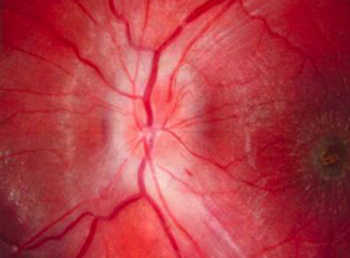

Primary care physicians play a central role in preventing and managing cardiovascular disease. Take a look at the variety of presentations in this week's photo quiz to test your knowledge.